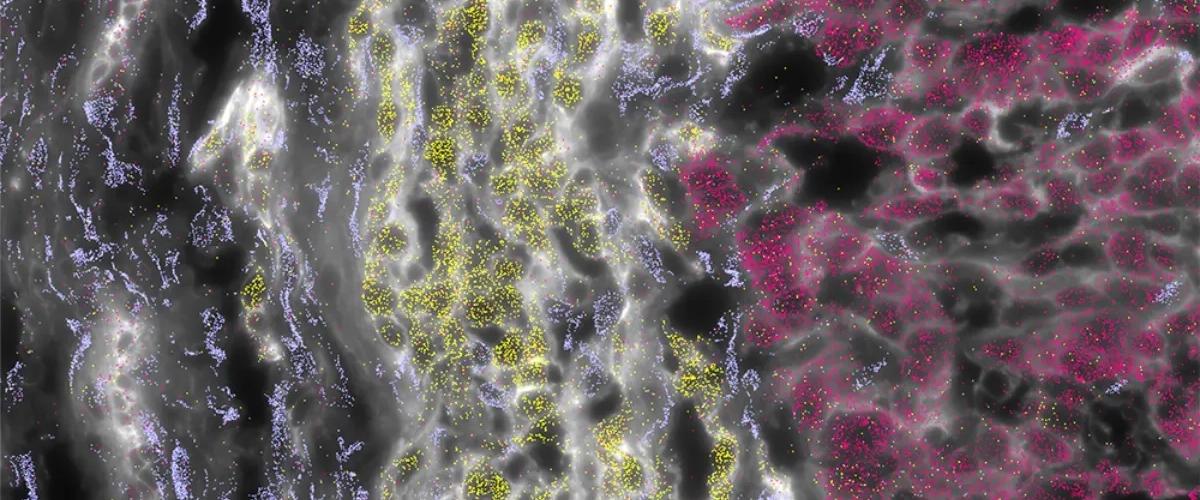

В рамках многочисленных исследований они выяснили, что у ФГК есть отчетливая подпись — набор из 301 активированного гена, который выделяет ее среди других типов опухолей печени. Эти уникальные изменения позволили рассуждать о необходимости определять рак не только по изменениям в ДНК, но и по изменениям в балансе активности белков в клетках. Сравнительный анализ был впервые проведен на крупной выборке из 220 образов ФГК и более 1200 образов других типов рака печени.